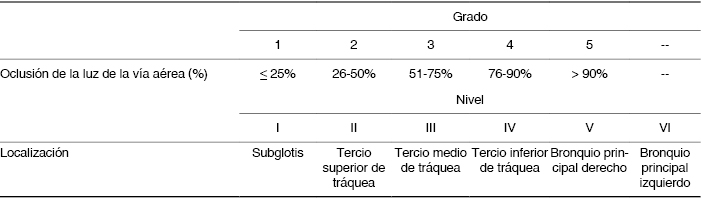

Definiciones: Con información obtenida del expediente broncoscópico, el grado y localización de la obstrucción fue clasificada según Freitag et al.(15) tal como se describe en la Tabla 1. Se consideró que existía mejoría satisfactoria después del tratamiento si había recuperación del lumen de la vía aérea con disminución de por lo menos un grado en la clasificación de Freitag asociada a mejoría de los síntomas.